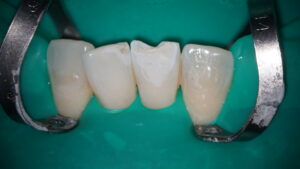

レジンを築成していきます。筆を使い、形態を整えます。

酸素はコンポジットレジンの重合阻害の原因になります。酸素と触れているレジンの表層は完全には固まらないのです。これはOxygen Inhibited Layerと呼ばれており、取り除くためにジェルで空気を遮断してから再度光を照射し再重合させていきます。このように一手間かけることが必要で、長期的に見た時にこれが大きな差となるはずです。